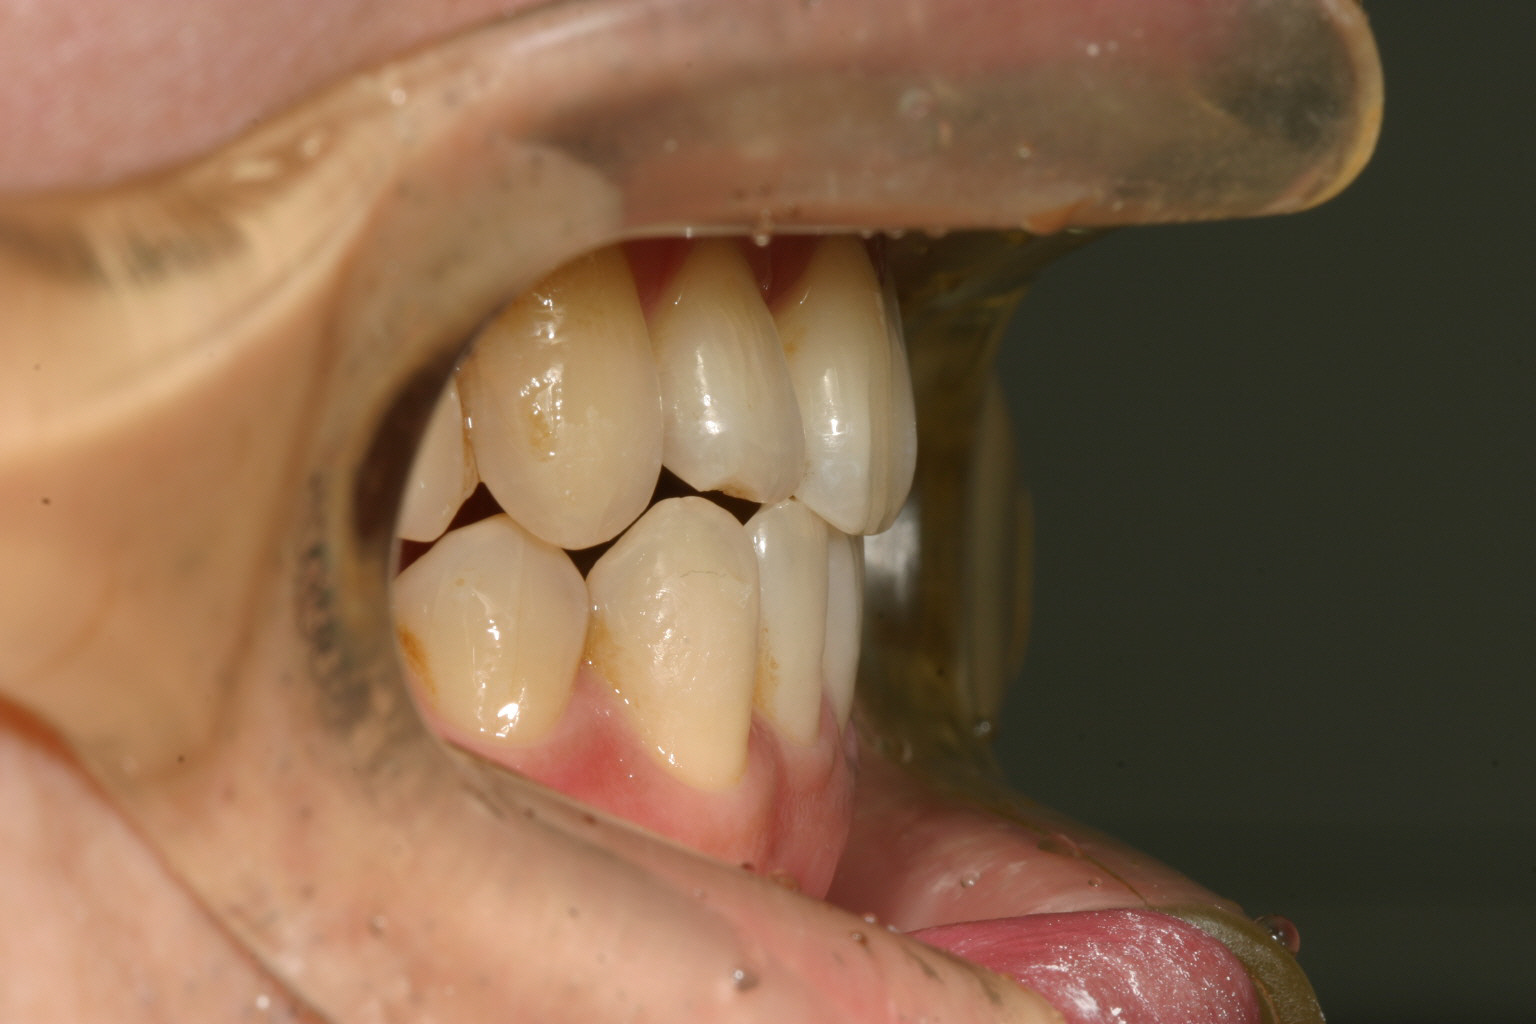

側面観ですがオーバージェットに問題無さそうですが叢生が有りますね~